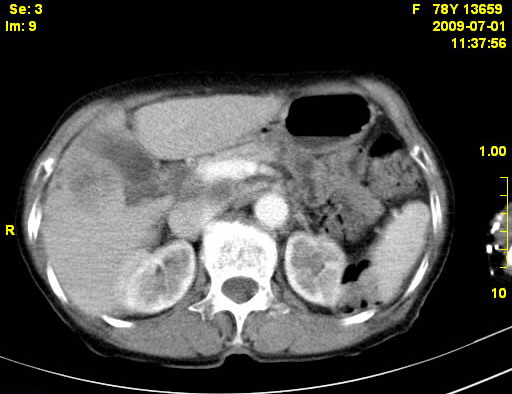

以下是引用zjzjr在2009-7-3 11:02:00的发言:[br]动脉期不均匀强化,门脉期及延迟期强化明显,肝门部见肿大淋巴结影,肝内胆管扩张.考虑肝右叶前段胆管细胞癌伴肝门淋巴结转移,胆内胆管扩张.慢性胆囊炎.

以下是引用dsl555在2009-7-4 10:59:00的发言:[br]考虑肝右叶前段胆管细胞癌伴肝门淋巴结转移,胆内胆管扩张.慢性胆囊炎. [br][br]支持。